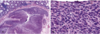

What type of adenocarcinoma is described here?

The neoplasm forms uniform gland structures, and the nuclei are localized to the basal half of the neoplastic cells.

Well-differentiated carcinoma

What level of differentiation?

The neoplasm is composed of complex glandular structures, with loss of polarity of the nuclei. Most colorectal carcinomas are moderately differentiated.

Moderately differentiated carcinoma

What level of differentiation?

The carcinoma shows minimal to no gland formation.

Poorly differentiated carcinoma